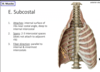

What muscle is indicated in the provided image?

Attachment?

Spans?

Fiber direction?

- If its crossing a rib then it has to be subcostas